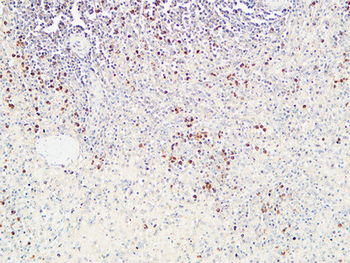

IHC staining of FFPE human lymph node with CD72 antibody (clone BU40). HIER: boil tissue sections in pH9 10mM Tris with 1mM EDTA for 20 min and allow to cool before testing.

IHC staining of FFPE human lymph node with CD72 antibody (clone BU40). HIER: boil tissue sections in pH9 10mM Tris with 1mM EDTA for 20 min and allow to cool before testing.